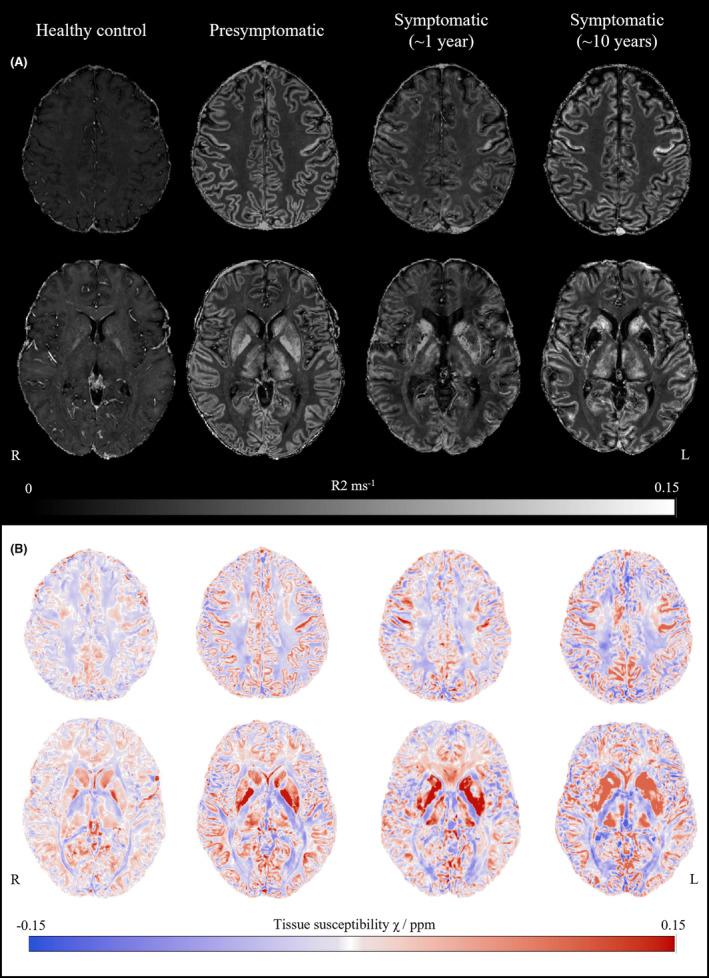

Neuroferritinopathy is a disorder of neurodegeneration with brain iron accumulation that has no proven disease-modifying treatments. Clinical trials require biomarkers of iron deposition. We examined brain iron accumulation in one presymptomatic FTL mutation carrier, two individuals with neuroferritinopathy and one healthy control using ultra-high-field 7T MRI. There was increased magnetic susceptibility, suggestive of iron deposition, in superficial and deep gray matter in both presymptomatic and symptomatic neuroferritinopathy. Cavitation of the putamen and globus pallidus increased with disease stage and at follow up. The widespread brain iron deposition in presymptomatic and early disease provides an opportunity for monitoring disease-modifying intervention.